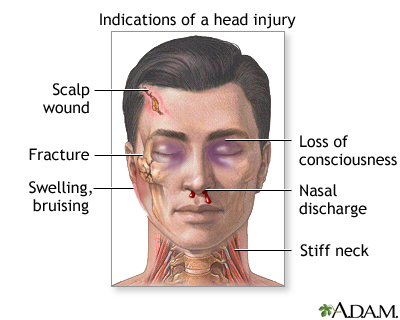

Symptoms of a head injury can occur right away or may develop slowly over several hours or days. Even if the skull is not fractured, the brain can hit the inside of the skull and be bruised. The head may look fine, but problems could result from bleeding or swelling inside the skull.

Some head injuries cause changes in brain function. This is called a traumatic brain injury. A concussion is a type of traumatic brain injury. Symptoms of a concussion can range from mild to severe.

Get medical help right away if the person:

- Becomes very sleepy

- Behaves abnormally, or has speech that does not make sense

- Develops a severe headache or stiff neck

- Has a seizure

- Has pupils (the dark central part of the eye) of unequal sizes

- Is unable to move all or part of an arm or leg

- Loses consciousness, even briefly

- Vomits more than once

Call 911 or the local emergency number right away if:

- There is severe head or face bleeding.

- The person is confused, tired, or unconscious.

- The person stops breathing.

- You suspect a serious head or neck injury, or the person develops any signs or symptoms of a serious head injury.